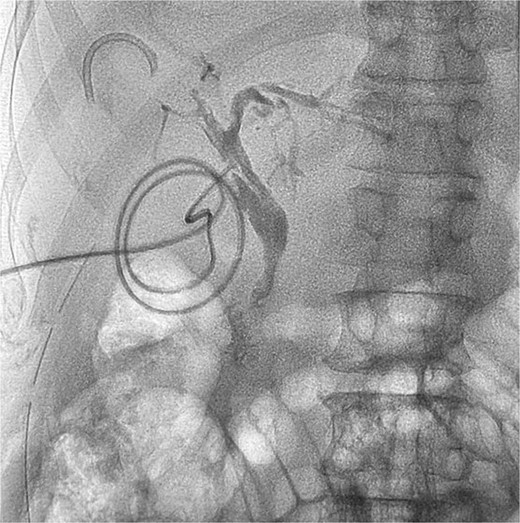

The primary indication for ERCP and stent placement in all patients was choledocholithiasis. At the current presentation, however, patients sought medical attention due to complications from retained stents. The majority (83.3%) exhibited clinical features of acute cholangitis, including upper abdominal pain, fever, and obstructive jaundice. Imaging confirmed the presence of CBD stones in all cases, with associated biliary sludge and stent blockage (Fig. 1).

T tube cholangiogram showing a residual fragment of the broken stent in the right anterior sectoral duct.